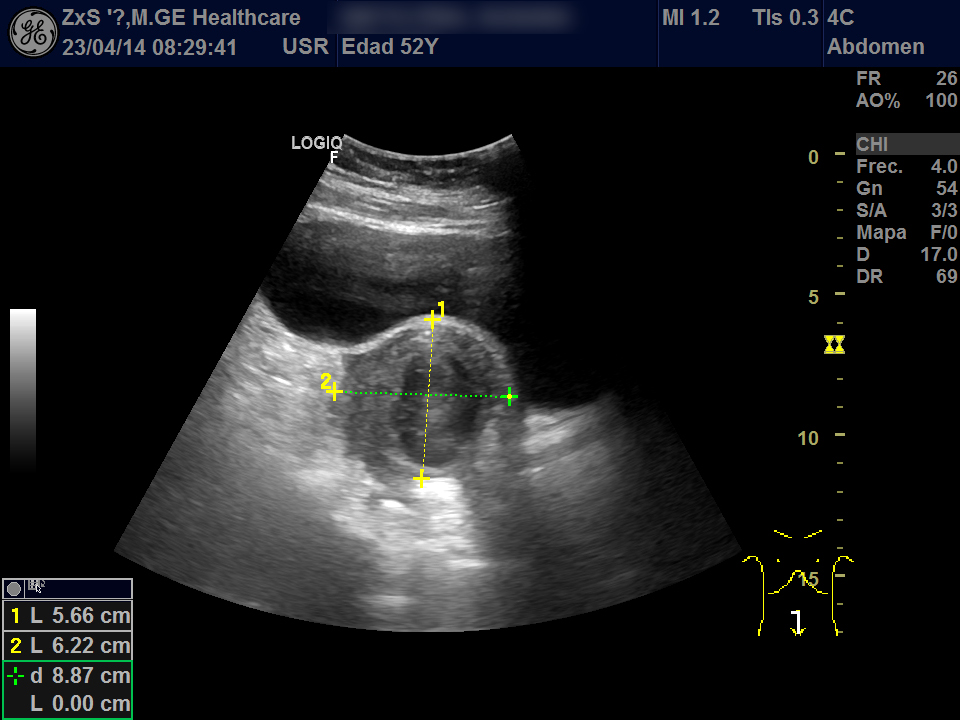

Hígado de bordes lisos y ángulo agudo, aspecto heterogéneo, no se observan LOES. Vía biliar extra e intrahepática no dilatada. Vesícula poco replecionada sin imágenes en su interior, Murphy ecográfico negativo. Ambos riñones de localización y tamaño normal. Buena diferenciación córtico-sinusal y en riñón derecho discreto aumento del tamaño de la pelvis renal compatible con hidronefrosis grado 2. Vejiga bien replecionada sin ecos en su interior. Se objetiva útero de tamaño normal con una imagen hiperecogénica que corresponde a DIU y en la zona derecha una lesión redondeada de aproximadamente 5,5 x 6,5 de diámetro de contenido heterogéneo que dudamos si puede corresponder a masa ovárica desconocida. Se deriva al hospital por sospecha de masa ovárica.